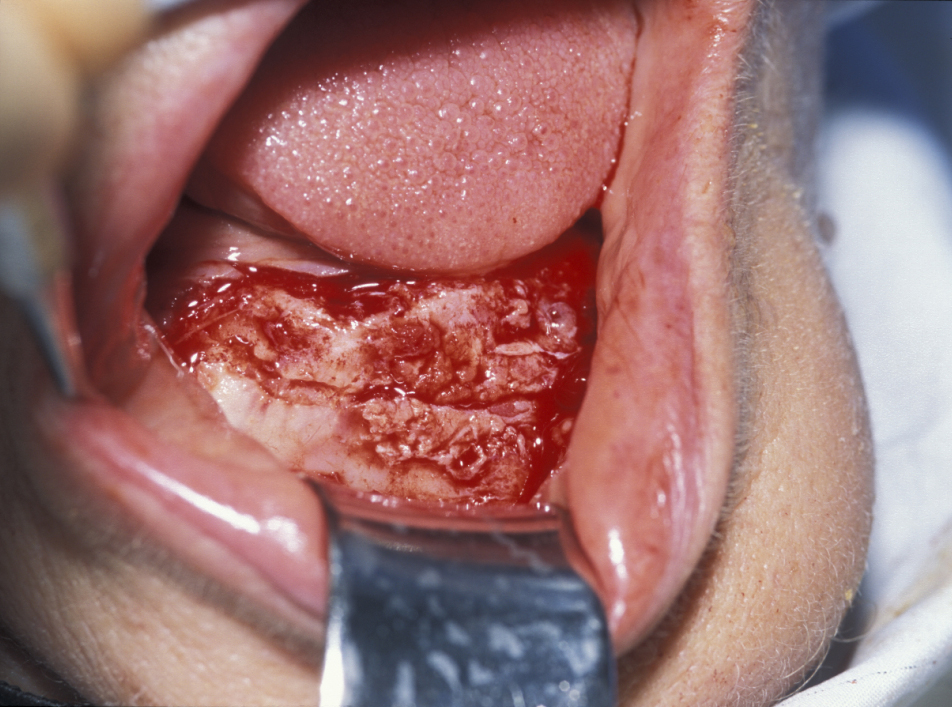

Marsupialization (cystostomy)

Large cysts in which enucleation may result in extensive local damage or patients who are unfit for more extensive surgery can be managed by marsupialization. This involves exposing the cyst lining and removing a small window from the lining. This is then sutured to the mucosa. The cavity can then be packed with an antiseptic dressing and regularly changed as the cavity heals from underneath. A step by step illustration of the procedure is shown in Figures 7 to 9.

Figure 7: Marsupialization of a cyst that is in contact with the overlying mucosa. The area of mucosa to be excised is marked (in purple).

Figure 8: The cyst lining is retained and in continuity with oral epithelium externalizing the cyst.

Figure 9: The defect is packed with iodoform gauze. This allows gradual resolution of the defect as new bone displaces the cavity lining.